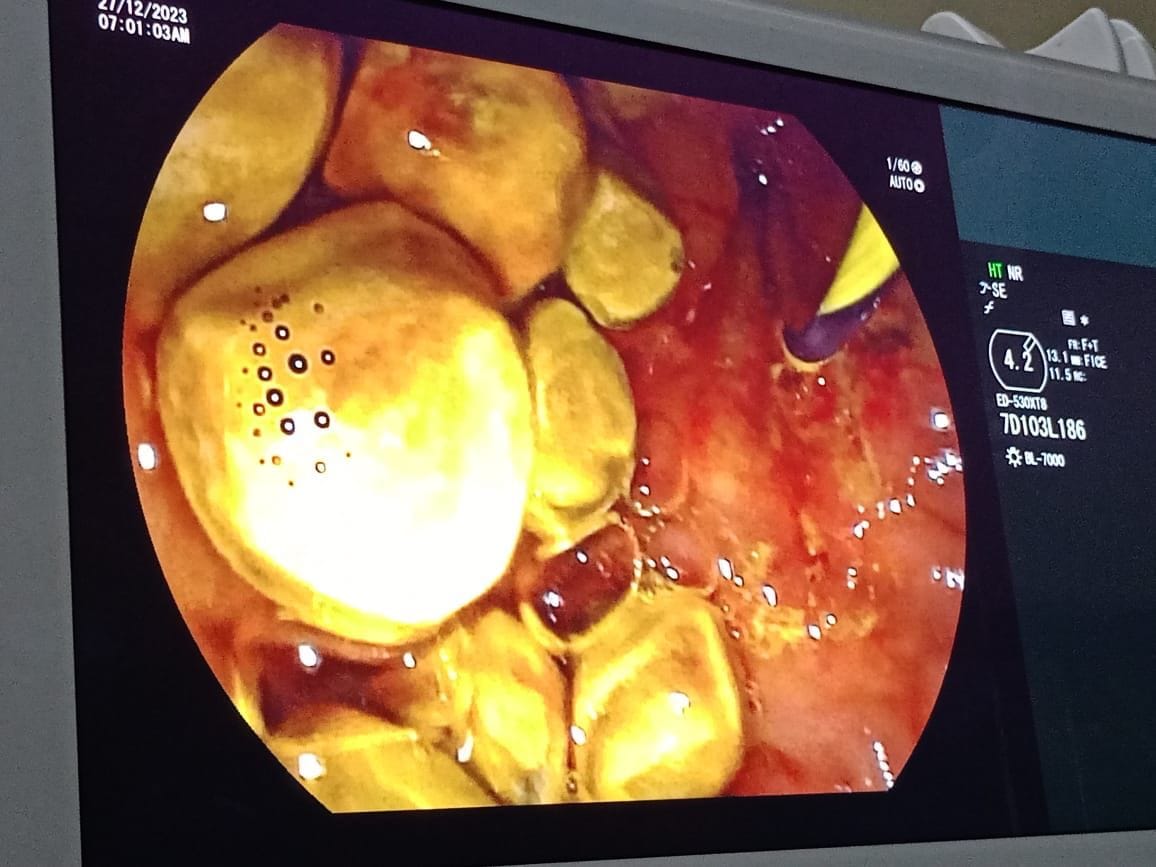

खोटेहाङ्ग गाउँ पालिका वर्ष ७२ पदमकुमारी राईको पित्त नलीमा रहेको ५० वटा जती ढुंगा विना शल्यक्रिया मुखबाट इण्डोस्कोप छिराएर झिकेर सफल उपचार भएको हो ।ग्यास्ट्रोइन्टेरोलोजिष्ट डा. मोहन खड्का नेतृत्वको चिकित्सा टोलीले उनको इआरसीपी प्रविधिबाट उक्त ढुंगा निकालेको थियो ।

करिव ५० वटा जति ६ देखि १० एम एम को ढुंगाहरु एकै प्रयासमा निकाल्न सफल भयौं डा. मोहन खड्काले भने । विरामीको अवस्था अहिने सामान्य रहेको र डिस्चार्ज हुने क्रममा रहेको छ ।